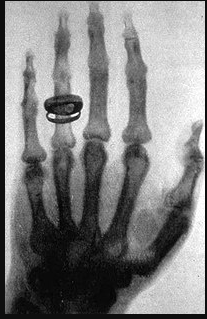

• WIHELM RONTGEN

WIHELM RONTGEN

Produjo y detecto la radiación electromagnética de los rayos X

con la ayuda de su esposa, a quien le pidió que colocara su mano izquierda sobre una placa de metal para poder “fotografiarla”